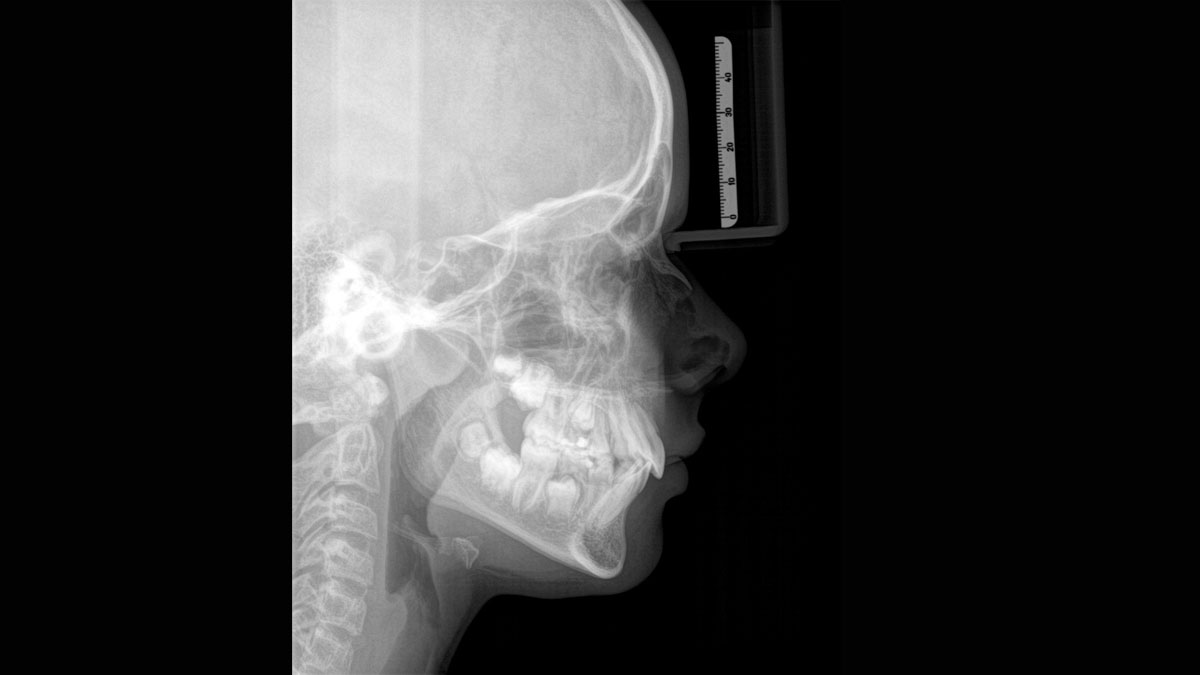

Es stehen mehrere Panoramaprogramme für Erwachsene und Kinder (Norm, Bissflügel, Nebenhöhlen usw.) zur Verfügung. Ein Ceph-Arm (links oder rechts) kann zum Zeitpunkt des Kaufs mitgeliefert oder später bei Bedarf nachgerüstet werden

Das Hauptziel bei der Verwendung eines Röntgengeräts ist für die meisten Praxen, das bestmögliche Bild für eine genaue und präzise Diagnose zu erfassen und den Prozess für die Patienten so komfortabel wie möglich zu gestalten. Der Orthophos S bietet Lösungen, um diese beiden Ziele zu unterstützen:

Eine Röntgenaufnahme muss sofort diagnostizierbar sein. Der Autofokus hilft dabei erheblich. Orthophos SL erfasst mehrere tausend Einzelbilder in einem Zyklus und erkennt automatisch scharfe Bereiche, um ein gleichmäßig scharfes Gesamtbild zu erzeugen. Der intelligente Autofokus erfordert keine manuellen Arbeitsschritte vor und nach der Erfassung.